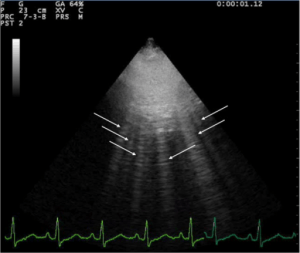

- Ultrasound

- Bedside to assess global function, B lines, assessment of IVC

- Formal TTE/TEE

Lung ultrasound of pulmonary edema

Lung ultrasound showing pulmonary edema.

- A lines and B lines

- A lines:

- Appear as horizontal lines

- Indicate dry interlobular septa.

- Predominance of A lines has 90% sensitivity, 67% specificity for pulmonary artery wedge pressure <= 13mm Hg

- A line predominance suggests that intravenous fluids may be safely given without concern for pulmonary edema

- B lines ("comets"):

- White lines from the pleura to the bottom of the screen

- Highly sensitive for pulmonary edema, but can be present at low wedge pressures